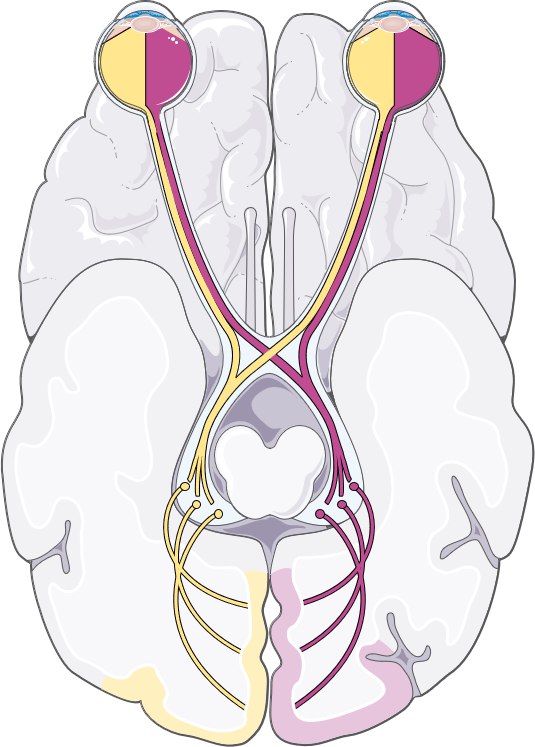

Секрет — в анатомии зрительных путей. Они частично перекрещиваются в области хиазмы, а затем идут в затылочную долю мозга — именно там формируется зрительное восприятие.

Если инсульт поражает правую затылочную кору, пациент теряет левые поля зрения обоих глаз — это называется гомонимная гемианопсия.

Если поражена левая затылочная доля, исчезают правые поля зрения. Это и есть правило зрительного перекреста.